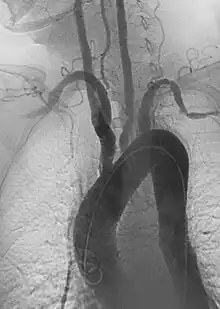

- Endovascular aneurysm repair: Placement of endovascular stent-graft across an aneurysm to prevent expansion or progression of the defective vessel.[6]

- Aortic aneurysms include thoracic, abdominal and thoracoabdominal aneurysms. Treatment strategies are customized depending on the location, size, rate of growth and extent of the aneurysm as well as the medical comorbidities of the patient. For example, an intact, small but slowly growing aneurysm may be safely monitored with serial imaging for months or years before elective repair is considered. Elective endovascular aortic grafting is now routinely attempted when possible. Endovascular aortic repair (EVAR) refers to treatment of an abdominal aortic aneurysm, while thoracic endovascular aortic repair (TEVAR) is performed on the thoracic aorta. A ruptured aneurysm may be taken emergently for open, endovascular or combination repair.